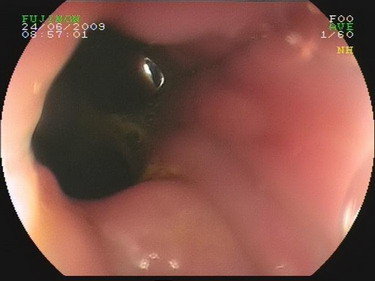

2009.6.24胃镜:

慢性浅表性胃炎,十二指肠淤滞症原因待查,肠系膜上动脉压迫综合症?(胃内可见胆汁样物反流,十二指肠球扩张,降部明显扩张,水平部远端似可见狭窄,持续充气肠腔不能打开。)